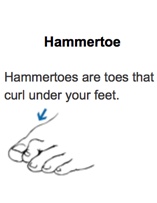

Motor nerves control muscles and give them their strength and tone. Peripheral neuropathy may also cause muscle weakness and loss of reflexes, especially at the ankle, leading to changes in the way a person walks. Foot deformities, such as bunions and hammertoes, may occur, as well as collapse of the midfoot, a condition known as Charcot foot.

The loss of foot structure may also cause shoes to rub against toes, causing sores. Blisters and sores may appear on numb areas of the foot because an injury goes unnoticed. If an infection occurs and is not treated promptly, the infection may spread to the bone, a condition known as osteomyelitis, and the foot may have to be amputated. Many amputations are preventable if minor problems are caught and treated in time.